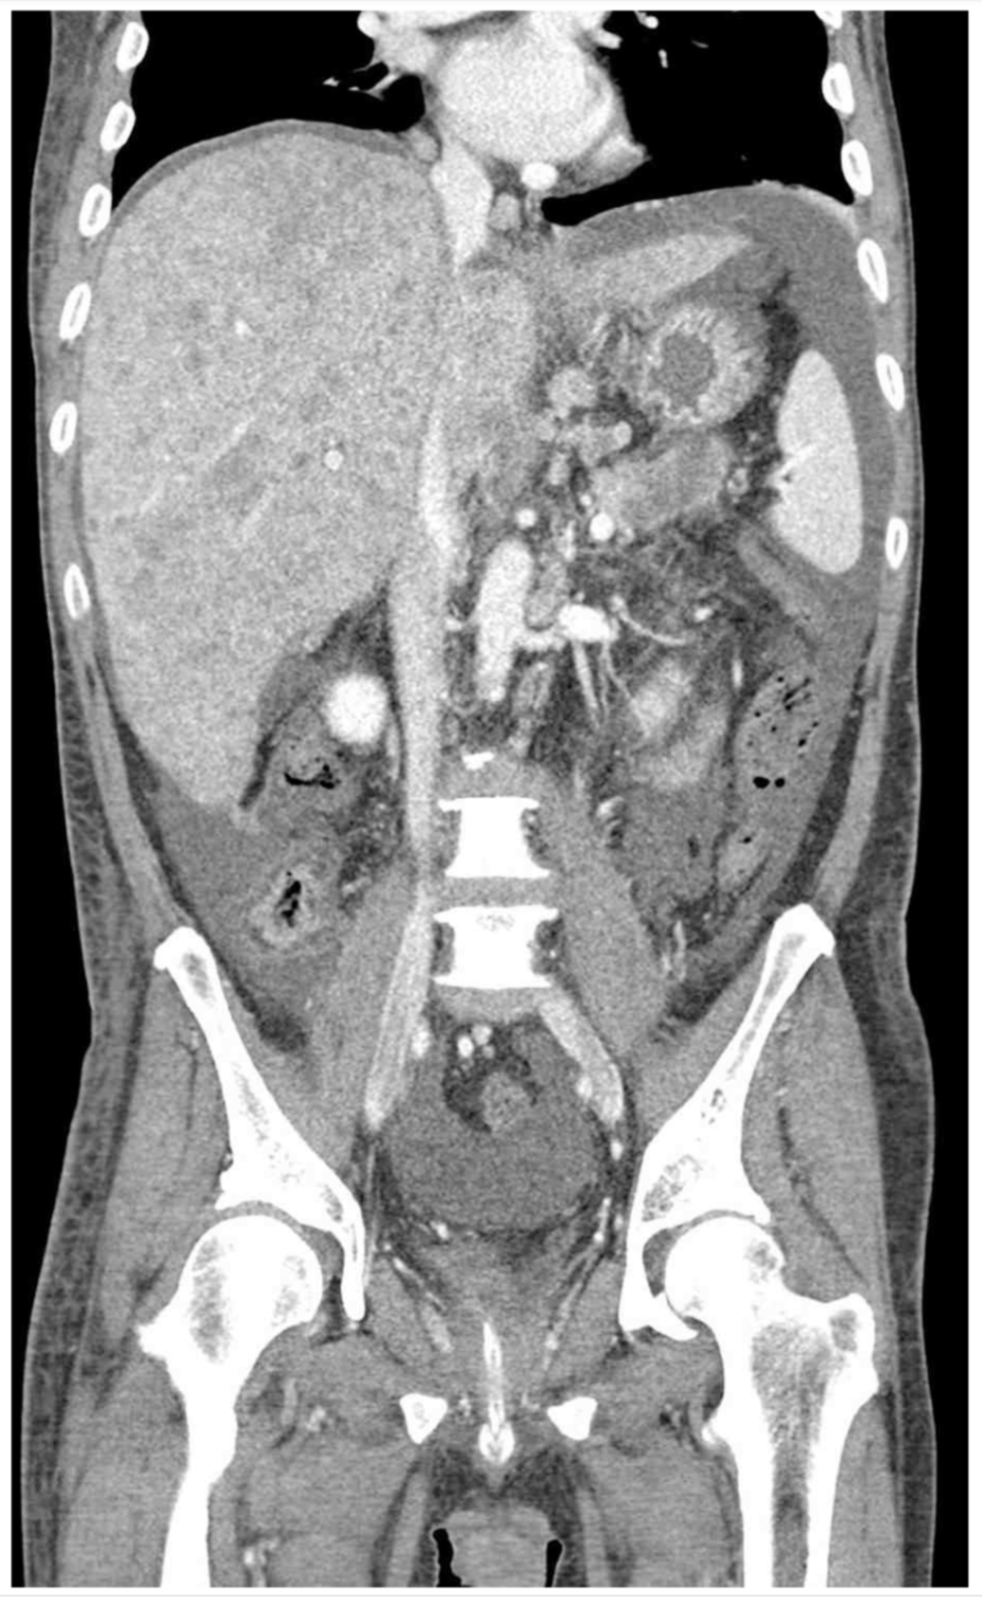

55세 남자가 10일 전부터 배가 아프고 불러진다고 응급실에 왔다. 2개월 전부터 변보기가 힘들고 변도 가늘어졌다고 한다. 혈압 130/85 mmHg, 맥박 105회/분, 호흡 22회/분, 체온 36.5 C이다. 배는 불러있고 압통과 반동압통은 없다. 혈액검사 결과는 다음과 같다. 복부 컴퓨터단층촬영 사진이다. 다음 검사는?

CT: Multifocal hepatic masses, hepatomegaly

• 원인 확인을 위해 시행한 CT에서 간에 다수의 mass가 관찰되는데, 현재 대장암이 의심되는 상황임을 고려할 때 전이성 암의 가능성이 높다. 앞선 Total bilirubin, AST/ALT, CA 19-9 elevation 모두 전이성 간암에서 나타날 수 있는 소견이다.

• 2개월 전부터 배변습관의 변화가 있는 환자에게서 CEA elevation 및 복부 CT상 간에서 다발성 종괴가 확인되므로 대장암 및 대장암의 간 전이가 강력히 의심된다. 따라서, 대장암 진단을 위해 대장내시경을 고려할 수 있다.